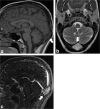

Calvarial lesions are often asymptomatic and are usually discovered incidentally during computed tomography or magnetic resonance imaging of the brain. Calvarial lesions can be benign or malignant. Although the majority of skull lesions are benign, it is important to be familiar with their imaging characteristics and to recognise those with malignant features where more aggressive management is needed. Clinical information such as the age of the patient, as well as the patient's history is fundamental in making the correct diagnosis. In this article, we will review the imaging features of both common and uncommon calvarial lesions, as well as mimics of these lesions found in clinical practice. TEACHING POINTS: • Skull lesions are usually discovered incidentally; they can be benign or malignant. • Metastases are the most frequent cause of skull lesions. • Metastatic lesions are most commonly due to breast cancer in adults and neuroblastoma in children. • Multiple myeloma presents as the classic "punched out" lytic lesions on radiographs. • Eosinophilic granuloma is an osteolytic lesion with bevelled edges.